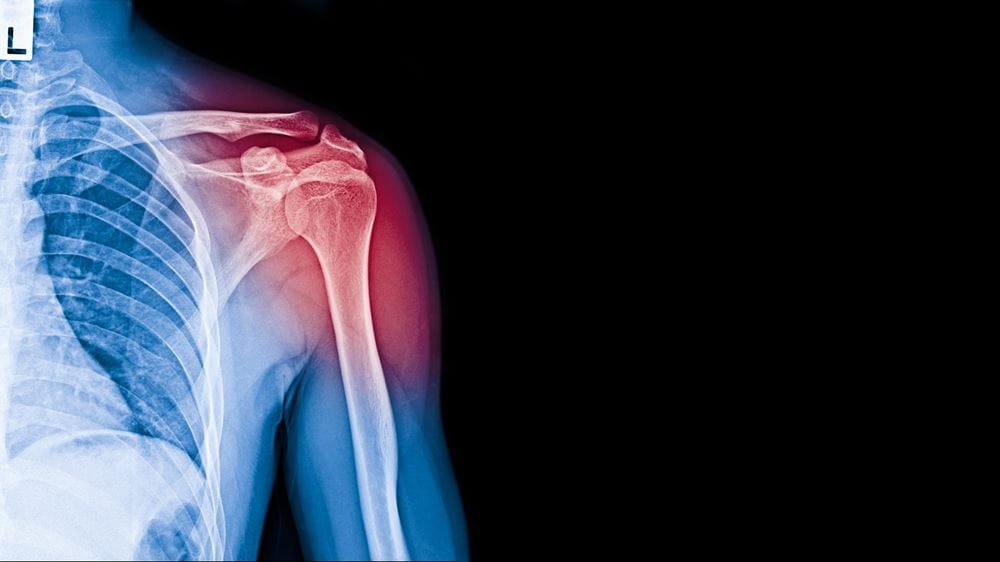

Shoulder & Elbow Problem

Speciality Shoulder,Elbow & Sports Medicine Specialist